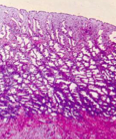

Professeur Rogue a écrit:L’utérus est donc formé de l’endomètre et en dessous du myomètre (et aussi de la troisième couche qui est l'adventice). Ce fameux endomètre (d'après ce que j'ai compris), est formé d'un épithélium cubique simple, qui est posé sur un stroma, le chorion, donc tout ça chorion + épithélium = endomètre (j’espère ne pas dire de bêtises à te faire arracher les cheveux)

Professeur Rogue a écrit:Ensuite, dans notre chorion, on va retrouver des glandes à différents niveau de notre chorion, chorion qui est composé de 3 couches, profonde, spongieuse et compacte (qui contient le plus de glandes), ces deux dernières prenant le nom de couche fonctionnelle. Donc ces couches au final si on dit que c'est de l’épithélium c'est faux ?

-"couche profonde = couche basale qui n'est pas expulsée pendant la menstruations et contient les cellules souches" donc ces cellules souches qui vont proliférer pour donner la couche fonctionnelle (c'est ce que je comprend)

-"couche fonctionnelle qui disparait pendant la menstruation"

Basale : adjacente au myomètre, effectivement elle contient des cellules souches (et je pense que c'est cette notion qui te gêne) MAIS elle n'est pas expulsée pendant les menstruations.

Spongieuse : qui va subir les variation.

Superficielle : où tes glandes vont être hyper-développés.

Au cours du cycle menstruel tu ne vas pas avoir une couche basale qui va se transformer en couche fonctionnelle. Mais tu vas avoir tes cellules qui vont proliférer ++ et donc ta couche compacte et spongieuse vont grossir et former la

couche fonctionnelle =>

ELIMINEE pendant les menstruations.

ta couche basale elle sera là pour toujours quoi ^^